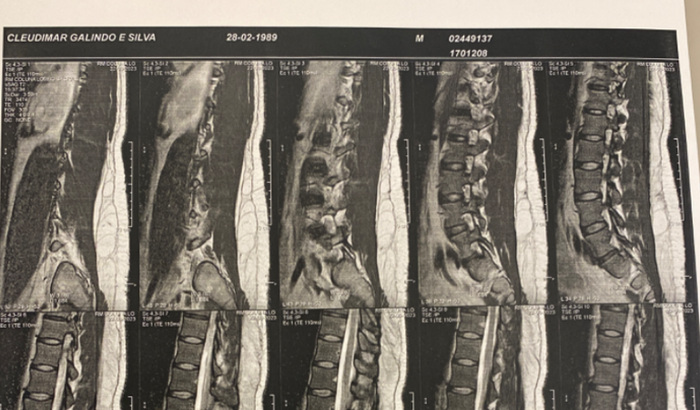

Pessoal, me chamo Cleudimar Galindo, nos últimos meses venho sofrendo seriamente com uma grande hérnia de disco na minha lombar, mesmo tentando vários tratamentos convencionais, nada funcionou e o problema só piora. Não tenho plano de saúde e depender do SUS será uma demora lente e agonizante, os médicos me falaram que posso perder o movimento de uma perna, devido a grande pressão no nervo, ocasionada por esta hérnia. Essa cirurgia se tornou urgente e não tenho o dinheiro suficiente para tal, venho de coração aberto, pedir para que você que recebeu a vaquinha ajude com qualquer valor, caso não possa ajudar com valores, faça uma oração. Isso já ajudará bastante. Deus te abençoe. Obrigado de coração!Â